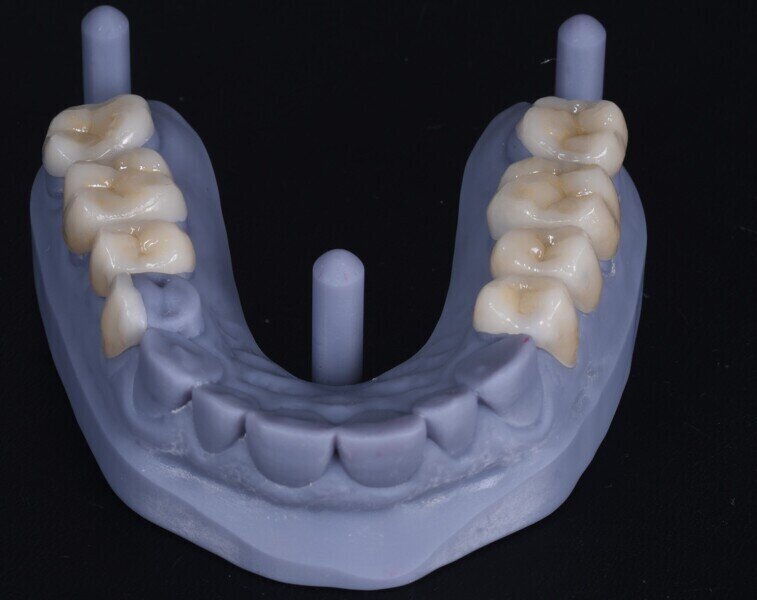

Dostavby byly navrženy v softwaru exocad (obr. 4) a pro jejich výrobu byl zvolen lithium disilikát (obr. 5). Výplně byly adhezivně fixovány v ústech pacienta. Po zvýšení VRO byla incizální okluze pacienta ideální pro rekonstrukci řezákového vedení, pro kterou bylo nutno zajistit pacientovi ortodontickou léčbu (obr. 6). Po ukončení ortodontické léčby byly opotřebené incizální hrany dolních řezáků obnoveny přímou dostavbou kompozitem (obr. 7).

Obr. 4a–f: Návrh laterálních dostaveb v programu exocad.

Obr. 5a, b: Zvýšení vertikálního rozměru okluze.